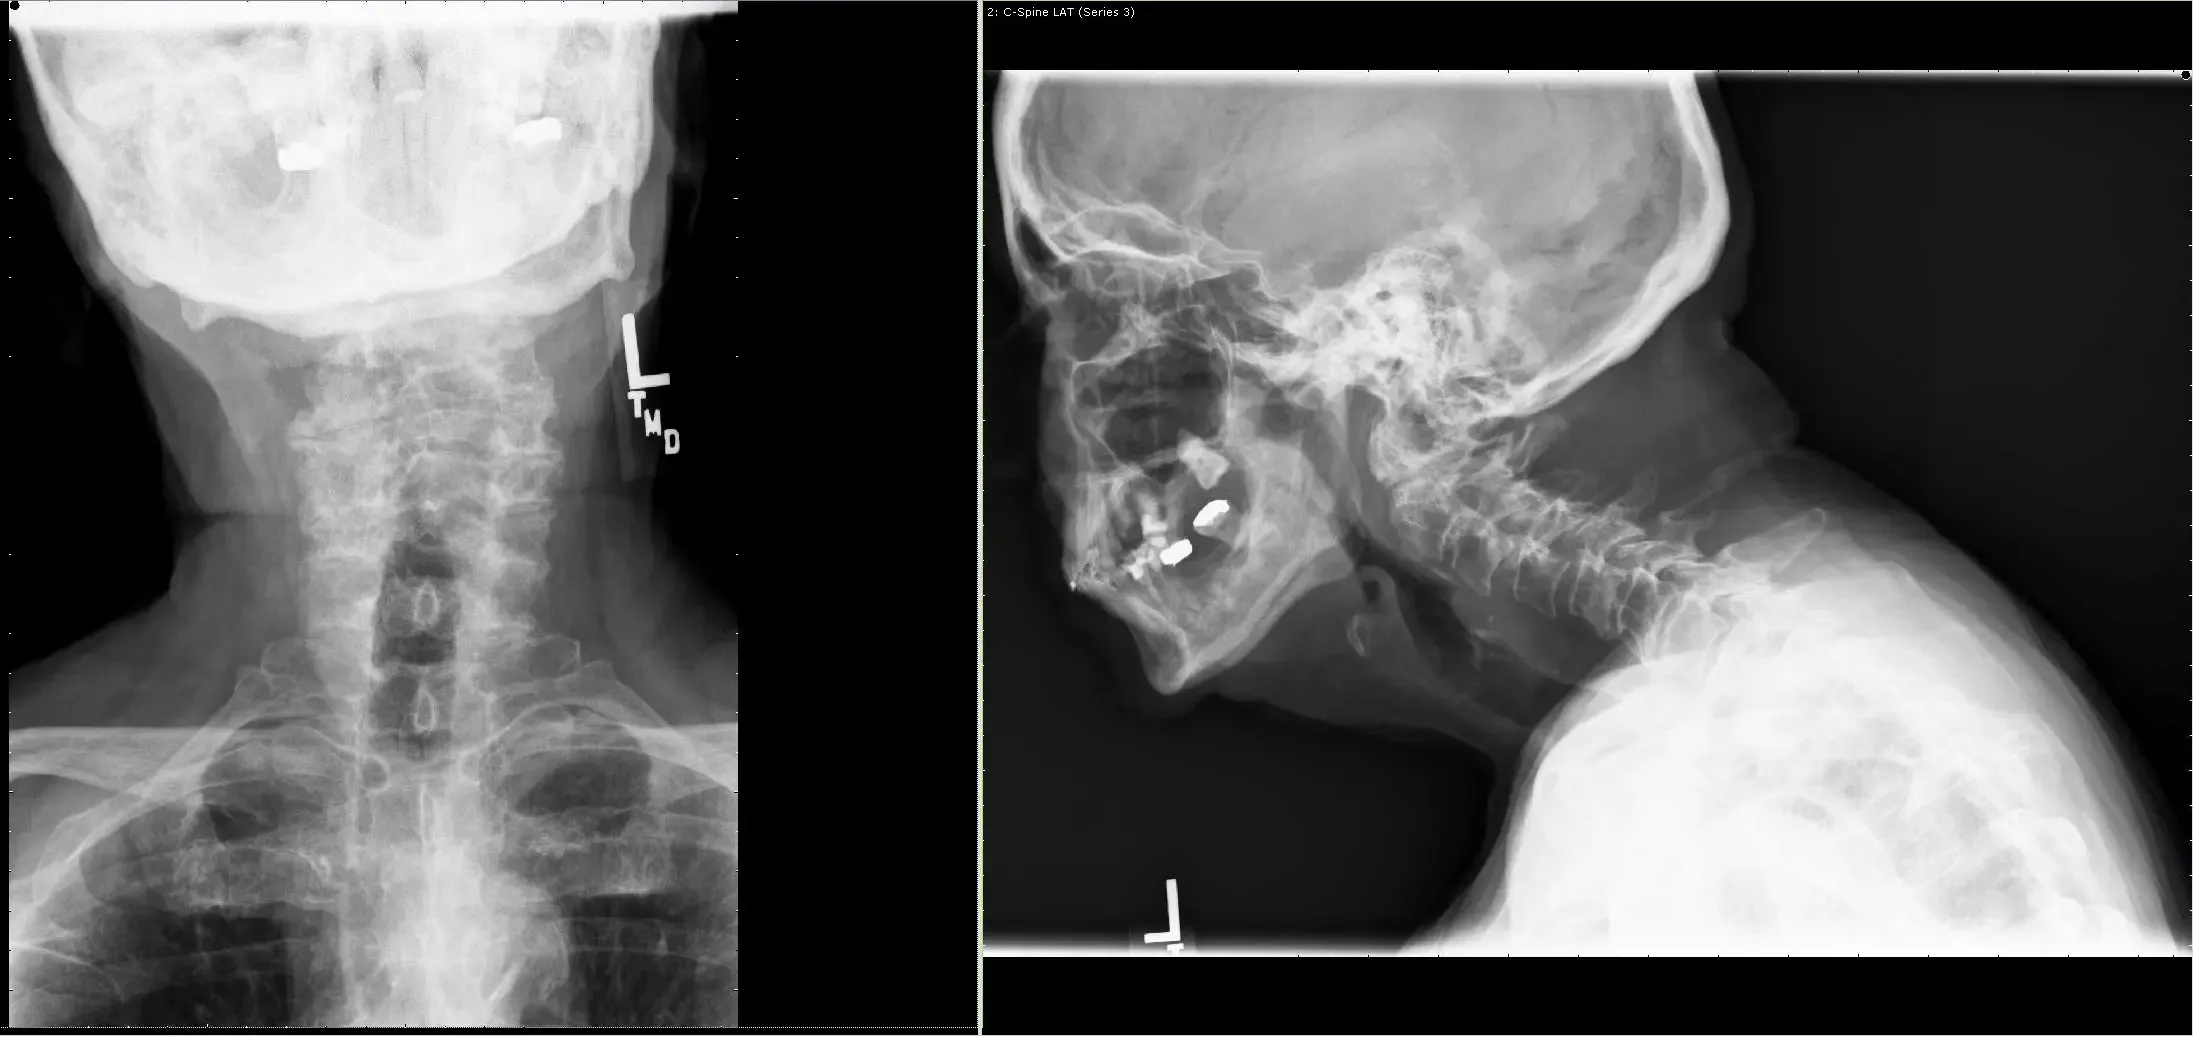

78 year old male presents with c/o bilateral hand clumsiness and balance problems. There is a remote history of fall about 4 years ago when he had neck pain and was treated in a cervical collar. There is no previous diagnosis of fracture.

He was having balance issues along with weakness in all 4 extremities. X rays, CT scan and MRI showed a non-union of odontoid fracture with pannus formation and fibrous union, instability with compression of spinal cord at C1-2 level.